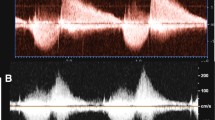

The pressure half time (PHT) (i.e. the time needed for the maximum transvalvular pressure gradient to decrease to its half value or the time interval for the peak velocity to reach 0.707 of the peak velocity value, in milliseconds) was measured by drawing a line along the regurgitation flow signal of the continuous wave (CW) Doppler tracing and by calculating the slope of this line according to current recommendations of the European Association of Echocardiography, as seen in Fig. 1a [24]. Previous studies have suggested PHT < 100 ms as the cut-off for significant PR [17, 18].

Doppler echocardiographic parameters. a PHT derived from CW Doppler echocardiography tracings. The deceleration slope of the PR (red line) represents the PHT. The PHT in this example is 118 ms, which suggests mild PR. b PRi measured with CW Doppler echocardiography. PRi is defined as the ratio of the duration of the regurgitation flow represented by line 2 (in this example 433 ms) divided by the total diastolic time, line 1 (in this example 646 ms). c The ratio of regurgitation jet width at the level of the PV (straight line) to PV annulus width (dashed line) measured during early diastole obtained by color-flow Doppler echocardiography. d DSTVI measured from the main pulmonary artery PW Doppler spectral tracing (red lines), is the area surface of the diastolic regurgitation flow (i.e. surface area 2) divided by the area surface of the systolic flow (i.e. surface area 1)

PR index (PRi) was calculated using the regurgitation time as percentage of the total diastolic time, derived from the CW Doppler tracings. The total diastolic time was defined as the time from the beginning of the diastolic flow curve to the beginning of the next systolic flow curve. The PR time was calculated from the beginning of the diastolic flow curve to the equilibration point at the x-axis, as seen in Fig. 1b. A low PRi corresponds with more severe regurgitation. Li et al. and Renella et al. have suggested PRi < 0.77 as the cut-off value between mild and significant PR [14, 17].